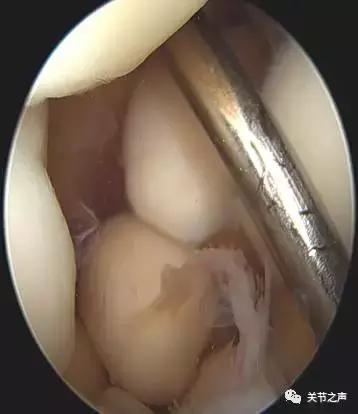

关节里长珍珠的症状:关节疼痛、卡压交锁例如:前不久,一位来自肇庆的许大姐因肩关节疼痛慕名来到暨南大学附属第一医院郑小飞主任门诊,X片显示他的肩关节长满了密密麻麻的“珍珠”。幸运的是,微创关节镜取“珍珠”是我们的看家本领,郑主任通过3个1cm的小切口就把他关节腔里的游离体全部取出,术后第二天开始康复功能锻炼。

除了肩关节,髋、膝、踝、肘、腕几乎全身各个关节都有可能长珍珠。